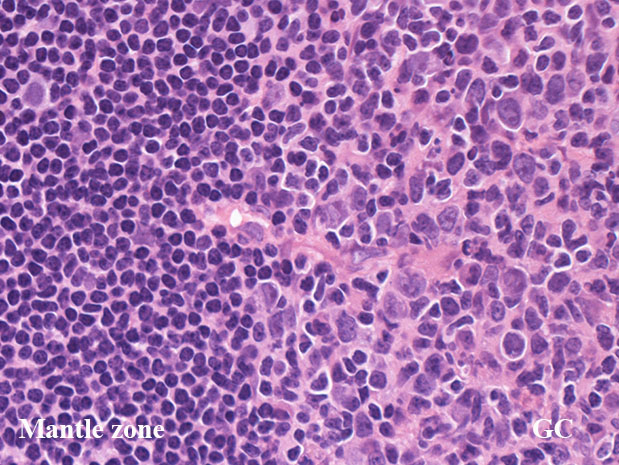

GC01.jpg

リンパ節の皮質cortexは, primary follicle(一次濾胞)とsecondary follicle(二次濾胞; 右図)から構成される.

secondary follicle;

胚中心(germinal center: GC)とmantle zoneをもつ.

mantle zoneはprimary follicle構成細胞と同じB細胞からなる. mantle zoneには厚い薄いがみられ, 薄いときはmantle zoneがないように見え, 子供のリンパ節に多い.

germinal center(GC)は, B細胞, T細胞, 抗原提示細胞, tindible-body macrophageが混在して構成されている. B細胞が優位に多く, small/ large cleaved cell(centrocytes)とlarge non-cleaved cells(centroblasts)が認められる。

正常胚中心のcentrocyte, centroblastsはbcl-2陰性であり, CD10, bcl-6が陽性となる. surface Igは低レベルであるが細胞質に通常 μ重鎖タイプ(IgM)Igが認められる.

T細胞はCD4+/ CD8-のhelper/inducer cellsであり, follicular (helper)T-cell:Tfhとよばれる. PD-1+, CXCL13+, CD57+.

高度に活性化された胚中心では, centrocyteとT細胞から構成される light zone (LZ)と増殖の盛んなcentroblastsとtindible-body macrophageの多いdark zone(DZ)が区分されるようになり, 極性(polarization)をもつといわれる.